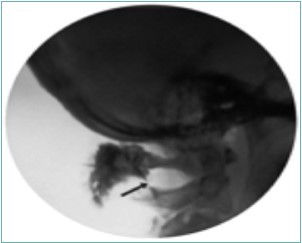

The largest of the three occipital nerves, the GON, arises from the dorsal root ganglion (DRG) of C2, running inferiorly between the arch of C1 (atlas) and the lamina of C2 (axis), lateral to the lateral atlanto-axial (AA) joint and deep to the inferior oblique capitus (IOC) muscle. The GON then curves medially and cephalad over the IOC Figure 1. As the GON travels cephalad up the neck, it travels over the posterior surface of the IOC to pierce the semispinalis capitis muscle, deep to the trapezius muscle, Figure 2 onto the posterior skull through a muscular sling formed by the aponeurosis of the sternocleidomastoid muscle (SCM) and the trapezius muscle at the skull attachment (the conjoined tendon) Figure 3. where it is joined laterally by the occipital artery. The GON can be found at this point lying in a palpable groove, immediately medial to the occipital artery and lateral to occipital prominence (the inion) Figure 1. There are several areas of potential entrapment of the GON

Figure 1.MRI anatomy of the upper cervical region. DI = digastric muscle; IO = inferior oblique muscle; LC = longus colli muscle; LE = levator scapulae muscle; MAS = masseter muscle; SC = semispinalis cervicis muscle; SCM = sternocleidomastoid muscle; SpC = splenius capitis muscle; TRAP = trapezius muscle; GA = great auricular nerve; GON = greater occipital nerve; GN = glossopharygeal nerve. LON = lesser occipital nerve; TON = third occipital nerve. Note the bifid spinous process of C2. (Image courtesy of Andrea Trescot, MD Clinical presentation

MRI anatomy of the upper cervical region. DI = digastric muscle; IO = inferior oblique muscle; LC = longus colli muscle; LE = levator scapulae muscle; MAS = masseter muscle; SC = semispinalis cervicis muscle; SCM = sternocleidomastoid muscle; SpC = splenius capitis muscle; TRAP = trapezius muscle; GA = great auricular nerve; GON = greater occipital nerve; GN = glossopharygeal nerve. LON = lesser occipital nerve; TON = third occipital nerve. Note the bifid spinous process of C2. (Image courtesy of Andrea Trescot, MD Clinical presentation